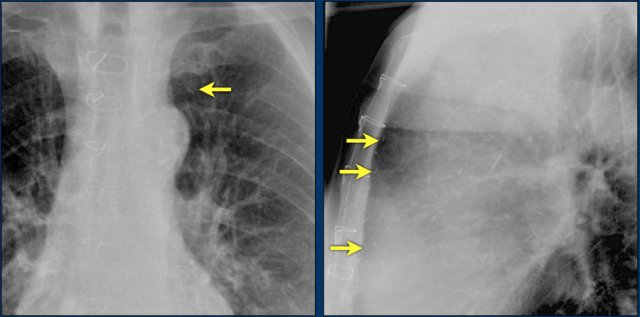

The images show a pacemaker with an atrial and ventricular lead.

The tip of the atrial lead is pointed upward and anteriorly, because the ideal position is in the right atrial appendage, where it is anchored within the coarse trabeculae.

The tip of the ventricular lead is positioned in the apex of the right ventricle, which is located to the left of the spine on a frontal chest X-ray and anteriorly on a lateral view.